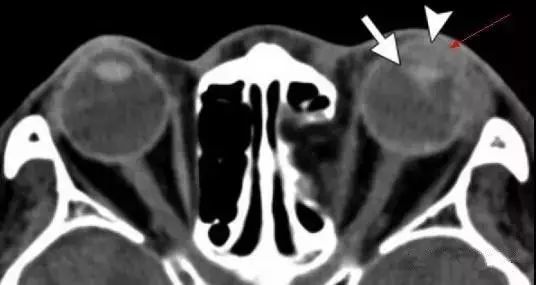

创伤性白内障

对眼球的钝性创伤也可能破坏晶状体囊 , 进而导致晶状体水肿并最终导致白内障的形成 。 白内障在临床检查时比较容易诊断 。

在CT上 , 与未受影响的晶状体相比较 , 受影响的水肿的晶状体可能表现为相对低密度 。 成熟的白内障可能表现为高密度影或含钙化